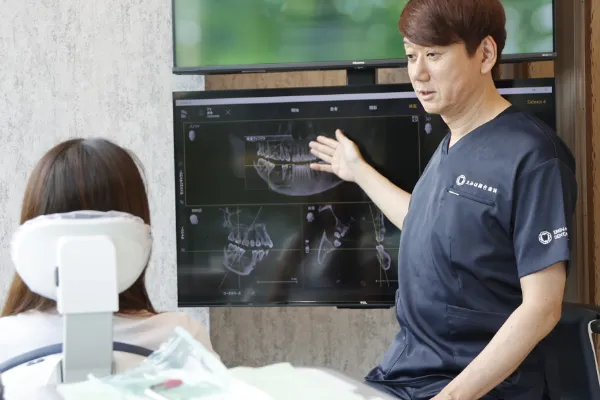

私は口腔外科専門医として20年以上の経験を積み、

「痛みを抑え、素早く、丁寧な治療」を提供してきました。

学会や研修会で最新技術を学び、

安全で信頼性の高いインプラント治療を行っています。

しかし、インプラント治療がすべてではなく、

患者様にとって最適な治療法を一緒に考え、

患者様の意向を尊重した治療を心掛けています。

痛みや不安を感じることがないよう、全力でサポートします。

インプラントで再び自由に食事を楽しんでいただけることを願っています!